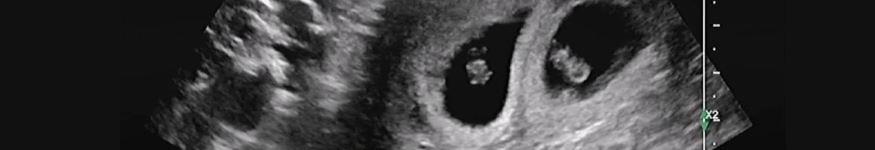

Als je in verwachting bent komt er veel op je af. Veel mensen voelen de neiging om je bang te maken met horrorverhalen. Als je in verwachting bent van een tweeling is dat niet anders. Want immers, elke tweeling wordt toch altijd veel te vroeg geboren? En ze wegen per baby minder dan een pakje suiker?